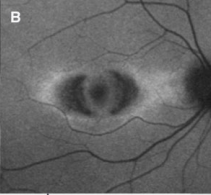

眼底蛍光検査

「ヒドロキシクロロキン網膜症のスクリーニング - 日本眼科医会」( https://www.gankaikai.or.jp/tsushin/files/20170124_1.pdf)より